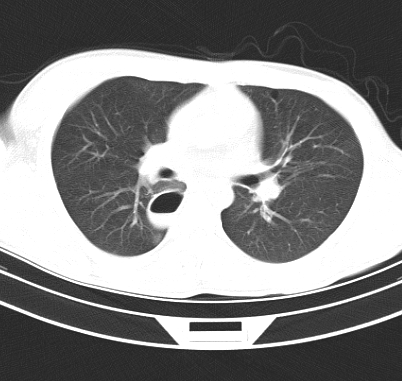

标题: CT19170:男 24岁,胸部外伤一周行CT检查 [打印本页]

男 24岁,胸部外伤一周行ct检查 未传纵隔窗

结合病史考虑肺挫伤后所致的肺气囊表现

结合临床考虑为右肺下叶背段撕裂伤。

首先考虑肺裂伤形成的液气囊肿.纵膈胸膜包裹性的液气胸可能性小,病变主要在肺内.

支持外伤性肺气囊。